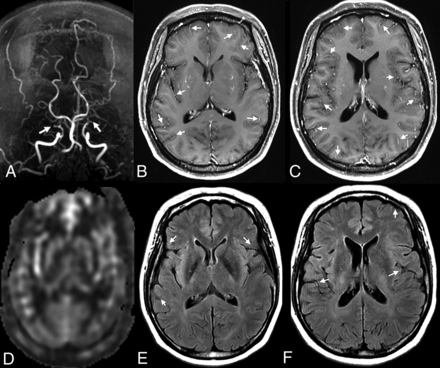

The ivy sign was defined on both CEMR and FLAIR images as continuous linear or punctate regions of leptomeningeal high signal intensity along the cortical sulci and subarachnoid space (Fig 1). Two radiologists, each with 2 years of experience, reviewed all CEMR and FLAIR images independently at 2 levels of the cerebral hemisphere (ganglionic and supraganglionic levels). The mean value was used as the final score for statistical analysis. We modified ASPECTS (Alberta Stroke Program Early CT Score, a semiquantitative method for estimating infarct size on CT) by omitting the deeper cerebral structures because they were not relevant to the assessment of leptomeningeal collaterals (only the M1–M6 cortical regions were included). Thus, each hemisphere was divided into 6 regions (3 regions for each level). The ivy sign score of each region was defined as follows: 0 represents no ivy sign, 1 represents the ivy sign reaching less than half of the region, and 2 represents the ivy sign reaching more than half of the region. The total ivy sign score of each hemisphere was defined as the sum score of 6 regions.8,9

Illustrative case of a 45-year-old woman with bilateral MMD. MRA reveals occlusion of bilateral MCA (white arrow) (A). CEMR shows better delineation of the ivy sign than FVH (white arrows) (B and C, E and F). The CBF of bilateral hemisphere shows no difference (D).